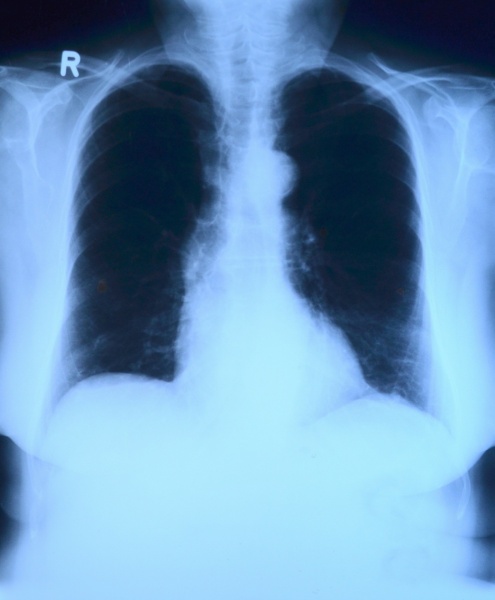

Komórkowy atlas płuc po śmierci z powodu Covid-19 pokazuje, dlaczego wirus tak szkodzi

Nowe badanie zaowocowało najdokładniejszym jak dotąd obrazem zmian w płucach po infekcji SARS-CoV-2. Wskazuje ono na trzy mechanizmy, prowadzące do uszkodzeń czy zgonów - i pokazuje, czym ta choroba różni się od innych.

Pacjenci, którzy zmarli z powodu Covid-19, padli ofiarą triady działających w płucach groźnych mechanizmów chorobowych - wynika z analiz naukowców kierowanych przez specjalistów z Columbia University i Herbert Irving Comprehensive Cancer Center. Wymieniają oni: gwałtowne zapalenie płuc, bezpośrednie uszkodzenie komórek płuc uczestniczących w wymianie gazowej (i ich osłabioną regenerację) oraz przyspieszone powstawanie blizn.